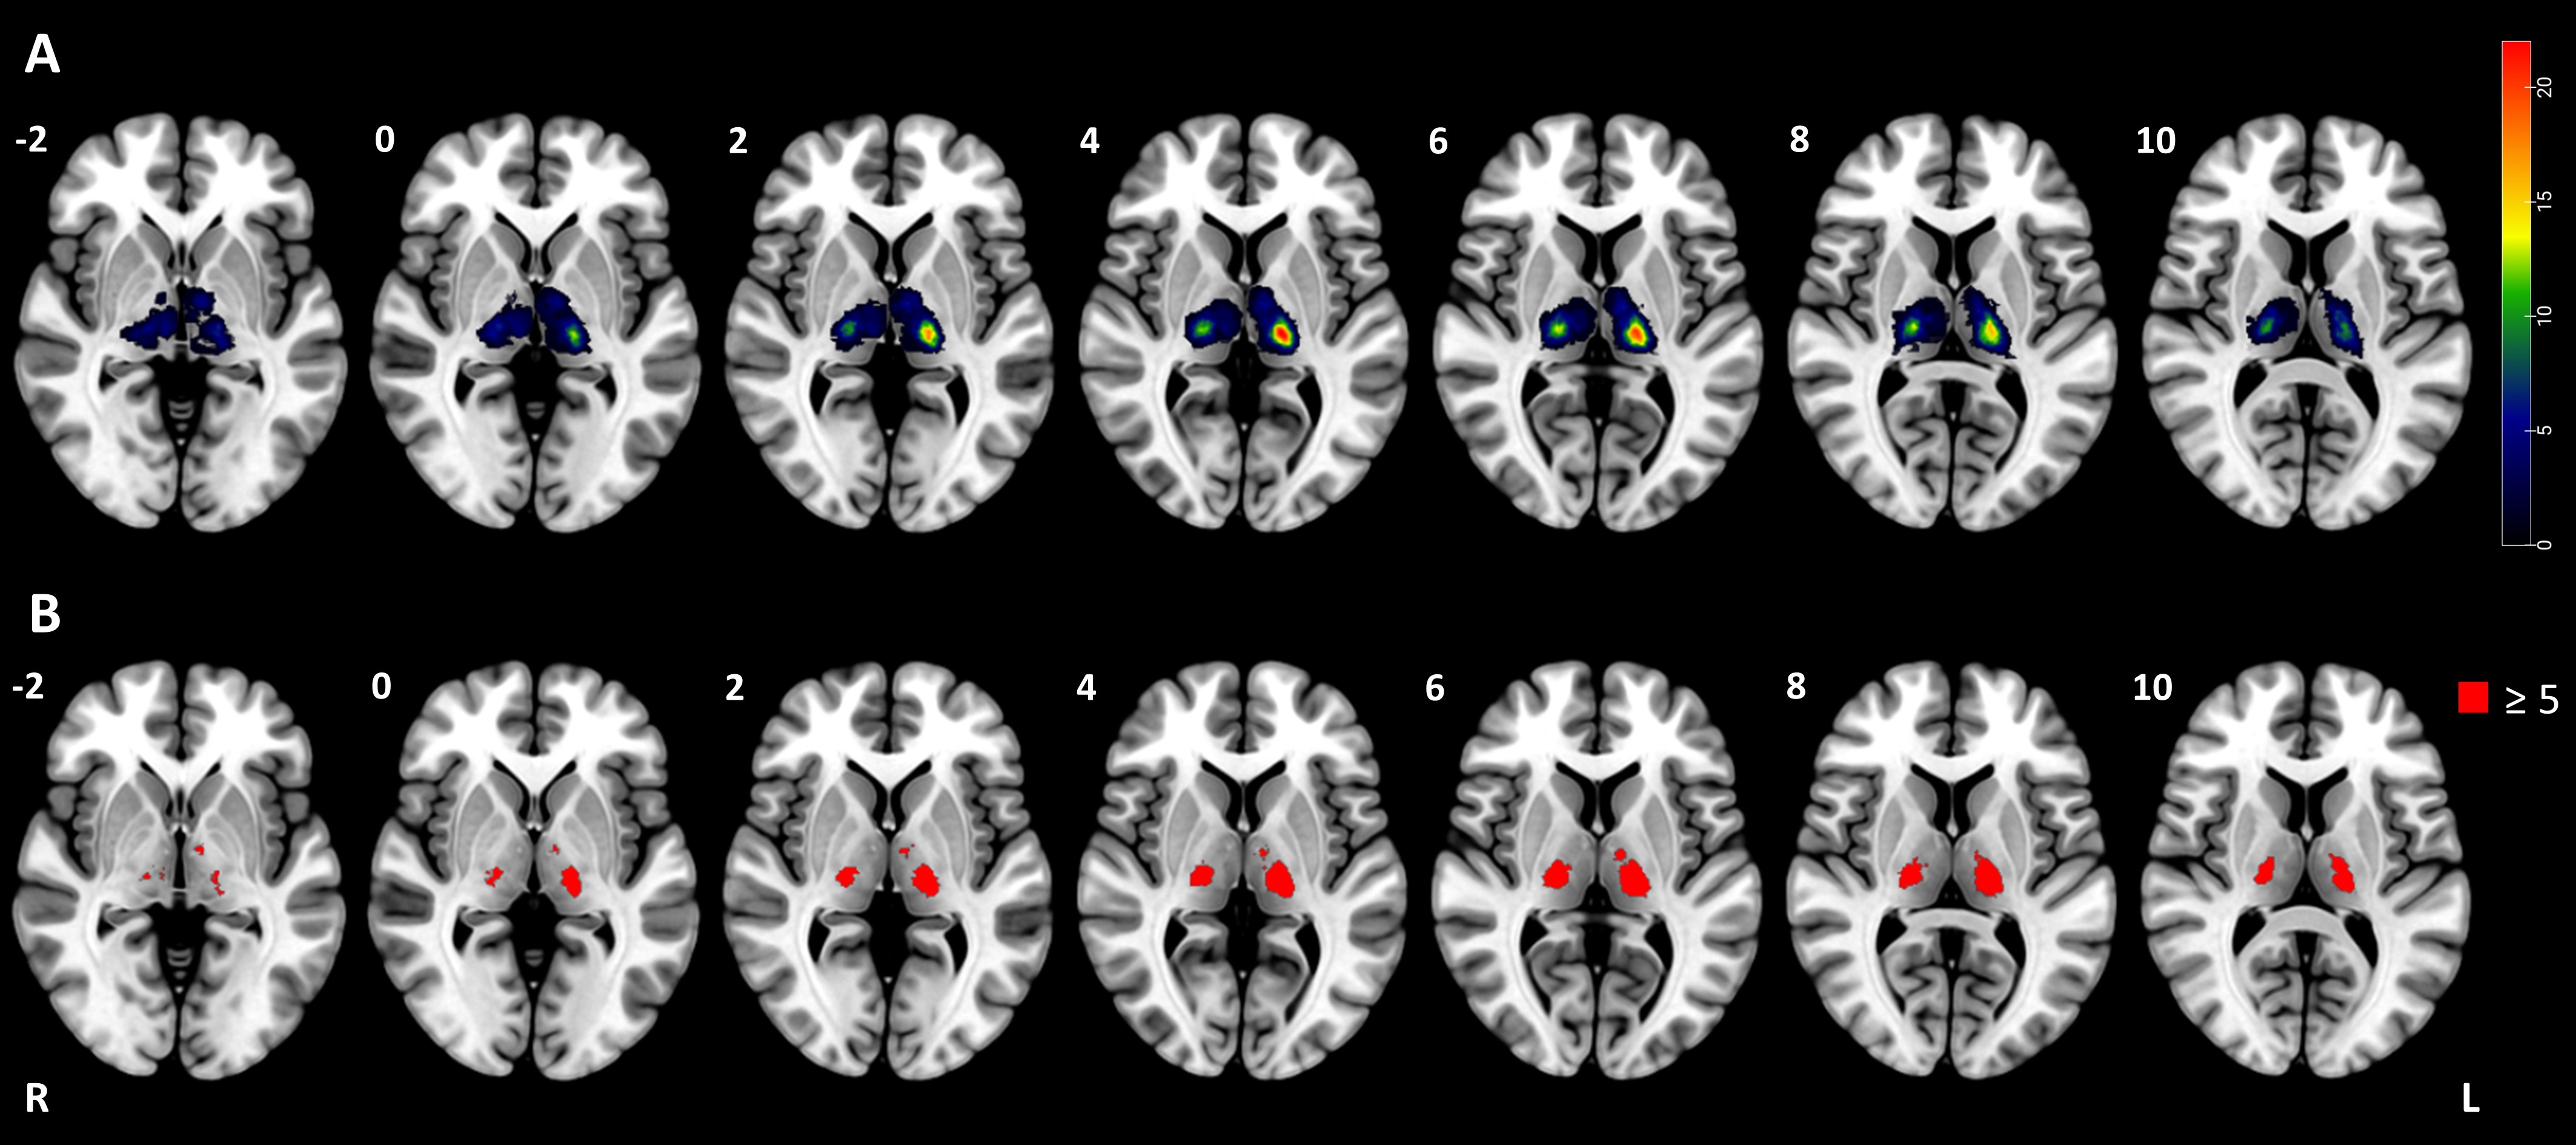

Method: This study recruited first-ever unilateral thalamic ischemic stroke patients. The Lille Apathy Rating Scale was used to characterize the appearance and severity of apathy. Patient’s lesion masks were embedded into normative connectome to generate functional or structural disconnection maps. Support Vector Regression-based Multivariate Lesion-Symptom Mapping and Disconnection-Symptom Mapping were employed to explore associations between lesion locations, structural and functional disconnections, and PSA.

Results: A total of 92 patients with thalamic infarction were included. No significant associations were found between thalamic lesion locations and PSA. However, structural disconnection in the anterior thalamic radiation and functional disconnection in the bilateral medial prefrontal cortex, bilateral inferior frontal gyrus, bilateral anterior insular cortex, right inferior parietal lobule, and right superior temporal gyrus were significantly associated with PSA.